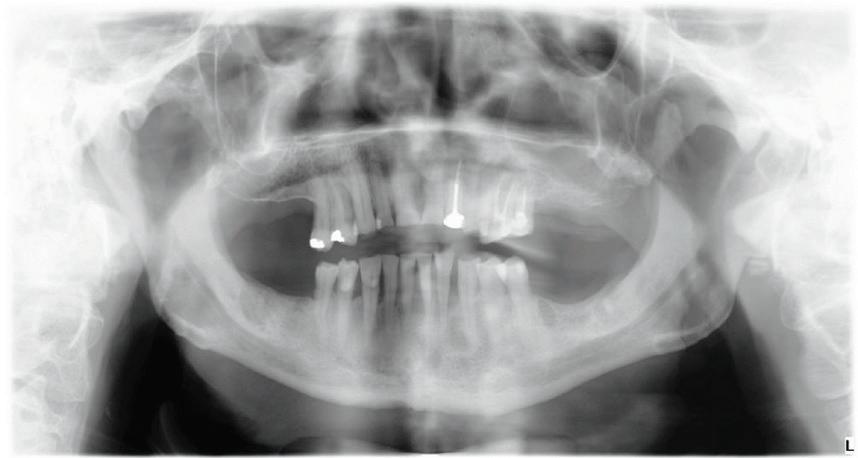

This gentleman presented with pain in his upper left quadrant. He had not been to a Dentist for many years and his dental experience had primarily been to have problematic teeth extracted (Fig. 1). As a result, he no longer had any of his molar teeth, but had been functioning well with his remaining premolar occlusion.

After his examination appointment, it was clear that the two premolars in the upper left quadrant had significant apical pathology and could not be predictably treated. His remaining dentition showed generalised attrition subsequent to dental erosion from gastric reflux, and his lower anteriors showed recession and some loss of periodontal support (Figs. 2, 3).